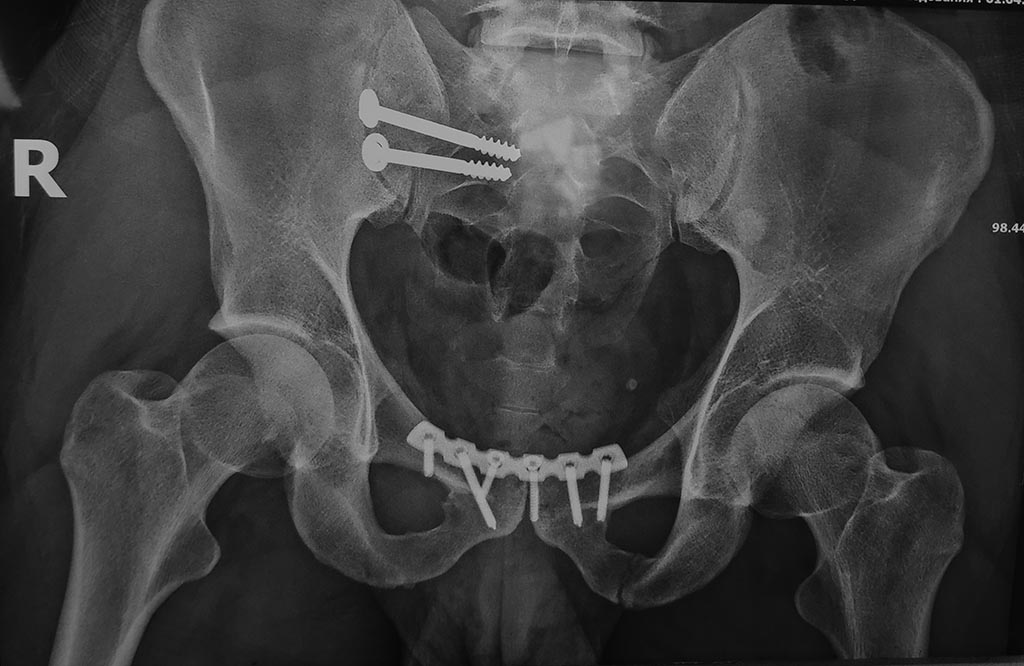

[Ortho] травма таза

вид после